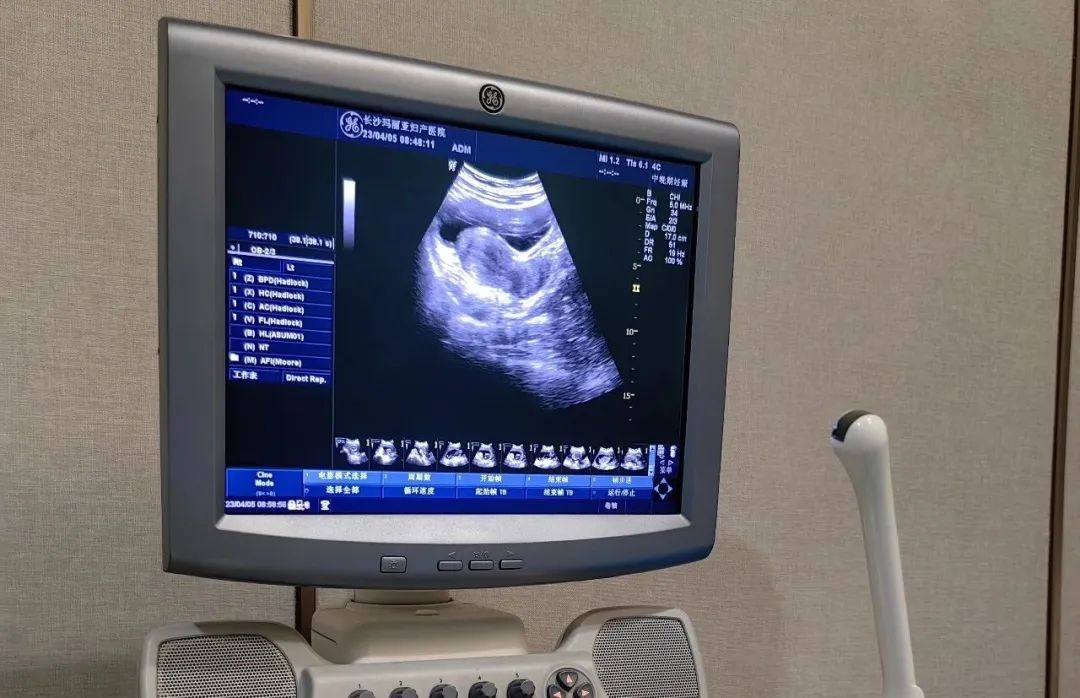

B超检查

B超能知道孕囊大小和发育情况。